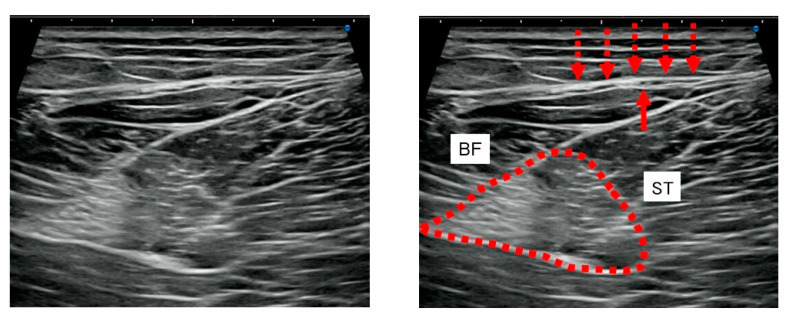

背景:腘绳肌腱损伤后的残余疼痛可能持续存在,尽管肌肉组织愈合并损害运动员寻求早期完全恢复。由于其原因尚不清楚,最近的注意力集中在筋膜功能障碍的作用和恢复筋膜活动的方法,即氢释放(HR),包括超声(US)引导下注射生理盐水。我们评估了HR治疗残余疼痛的临床疗效,并确定了其潜在的病理机制。方法:选取腘绳肌损伤后残余疼痛≥8周的7例患者,年龄17-49岁。所有患者均表现出局部压痛和超声显示腱膜筋膜(APF)周围的筋膜增厚。6.0 mL盐-利多卡因溶液(0.17%利多卡因)进行HR,靶向apf周围疏松结缔组织。采用数值评定量表(NRS)对HR前后疼痛进行评估。被动直腿抬高(SLR)用于评估松紧度。结果:术后NRS评分由10分降至0.86分,差异有统计学意义(p = 0.017)。4名患者需要一次HR会议;其中三个需要两到四个疗程。hr后,所有患者的松紧度均有改善。股后短轴超声显示压痛区APF筋膜增厚,包括股后皮神经(PFCN)。随访期间无不良事件及复发(平均6.6个月)。结论:HR靶向周围pfcn - apf可有效减轻腘绳肌损伤后的残余疼痛。这些发现支持了“神经周围筋膜疼痛”的概念,即持续性疼痛不是源于直接的神经损伤或经典的肌筋膜疼痛综合征,而是源于周围筋膜的功能障碍。

Background: Post-hamstring-injury residual pain may persist despite muscle-tissue healing and impairs athletes seeking early full recovery. Given their unclear cause, recent attention has focused on the role of fascial dysfunction and a method to restore fascial mobility, namely, hydrorelease (HR), involving the ultrasound (US)-guided injection of saline. We evaluated the clinical efficacy of HR for treating residual pain and ascertained the underlying pathological mechanisms. Methods: Seven patients (aged 17-49 years) with residual pain ≥8 weeks after hamstring injury were included. All exhibited localized tenderness and US findings of fascial thickening around the aponeurotic fascia (APF). HR with 6.0 mL saline-lidocaine solution (0.17% lidocaine) was performed and targeted the peri-APF loose connective tissues. Pain was evaluated using a numerical rating scale (NRS) before and after HR. Passive straight leg raise (SLR) was used to assess tightness. Results: Post-HR, the mean NRS score significantly decreased from 10 to 0.86 (p = 0.017). Four patients required a single HR session; three required two-four sessions. Post-HR, the tightness of all patients improved. Short-axis US of the posterior thigh revealed APF fascial thickening in the area of tenderness, including the posterior femoral cutaneous nerve (PFCN). No adverse events or recurrence occurred during the follow-up (mean: 6.6 months). Conclusions: HR targeting the peri-PFCN-APF effectively reduced residual pain following hamstring injury. These findings support the concept of "Perineural fascial pain"-a pathology wherein persistent pain originates not from direct nerve damage or classical myofascial pain syndrome but rather from the dysfunction of the surrounding fascia.